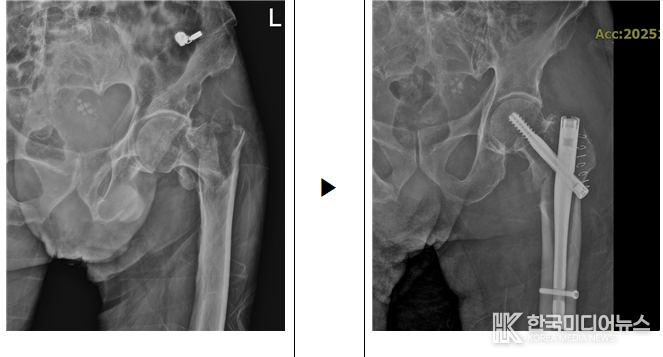

[ 한국미디어뉴스 이원영 기자 ] 인성의료재단 한림병원은 100세 초고령의 고위험 환자에게 시행한 대퇴골 골절 수술을 성공적으로 마쳤다고 14일 밝혔다.

해당 환자는 길에서 쓰러져 있는 것을 행인이 발견해 119로 이송되었으며, 외상 없이 갑작스럽게 증상이 발생해 본원 응급실로 내원했다. 초고령 환자의 경우 마취 및 수술 과정에서 합병증 위험이 매우 높기 때문에, 철저한 사전 준비와 다학제 협진이 필수적이다.

수술은 한림병원 정형외과 김은열 과장을 중심으로 척추·관절센터, 심장내과, 흉부외과, 중환자실 등 여러 전문의료진이 긴밀히 협력하여 진행됐다. 환자는 수술 후 중환자실에서 집중 치료를 받은 뒤, 현재 안정적인 회복세를 보이며 재활치료를 통해 일상 복귀를 준비하고 있다.